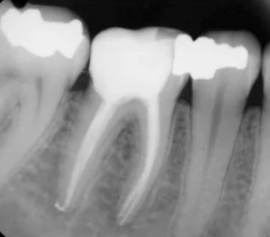

Tooth Caries

Patient: David H., 51